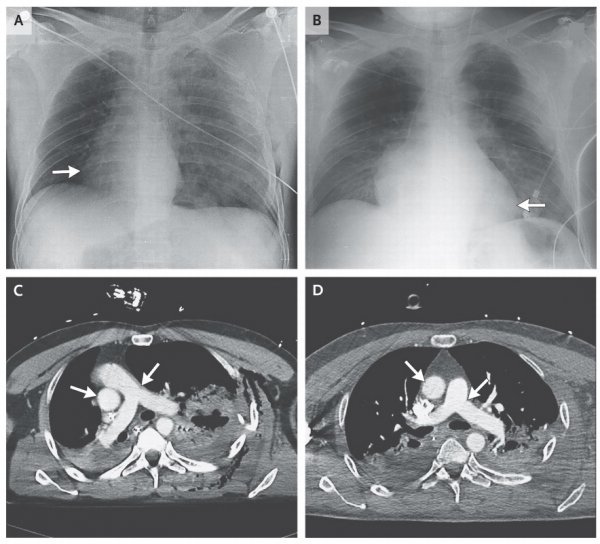

据悉,急诊室医生在为这名在摩托车事故中严重受伤的男子听心音和心律时,惊奇地发现他的心脏不在正常的位置上。医生在发表在《新英格兰医学期刊》的诊断报告中称,X光和CT扫描图显示,这名伤患的心脏在90度大扭转后移位到了右胸腔。

丰塔纳称,车祸中伤者身体剧烈扭曲从而造成其心脏旋转跑偏的推测看似逻辑合理,但实际上,这样诡异的变化并未发生在车祸当场,而可能在几分钟甚至一小时后才发生。充斥在胸腔里的空气或许就是心脏移位的推手,因为医生发现,该男子胸腔里累积了因肺部受伤而泄露出来的空气。在抽干这些气体后,他的心脏弹回了左胸,并在24小时后完全回到了它原本的位置。